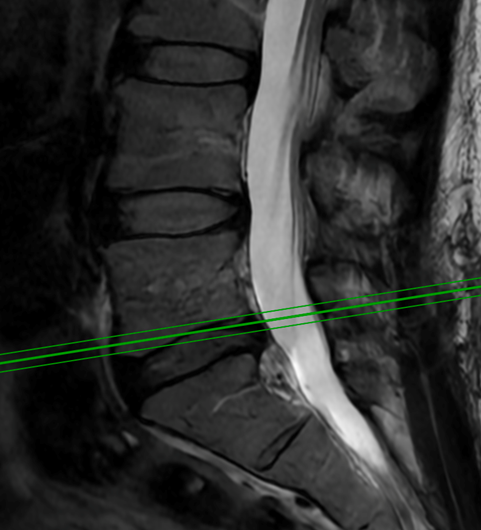

Spine:

Central Cord Syndrome

Author: Yusef Imani M.D., F.A.A.N.S., Read More!